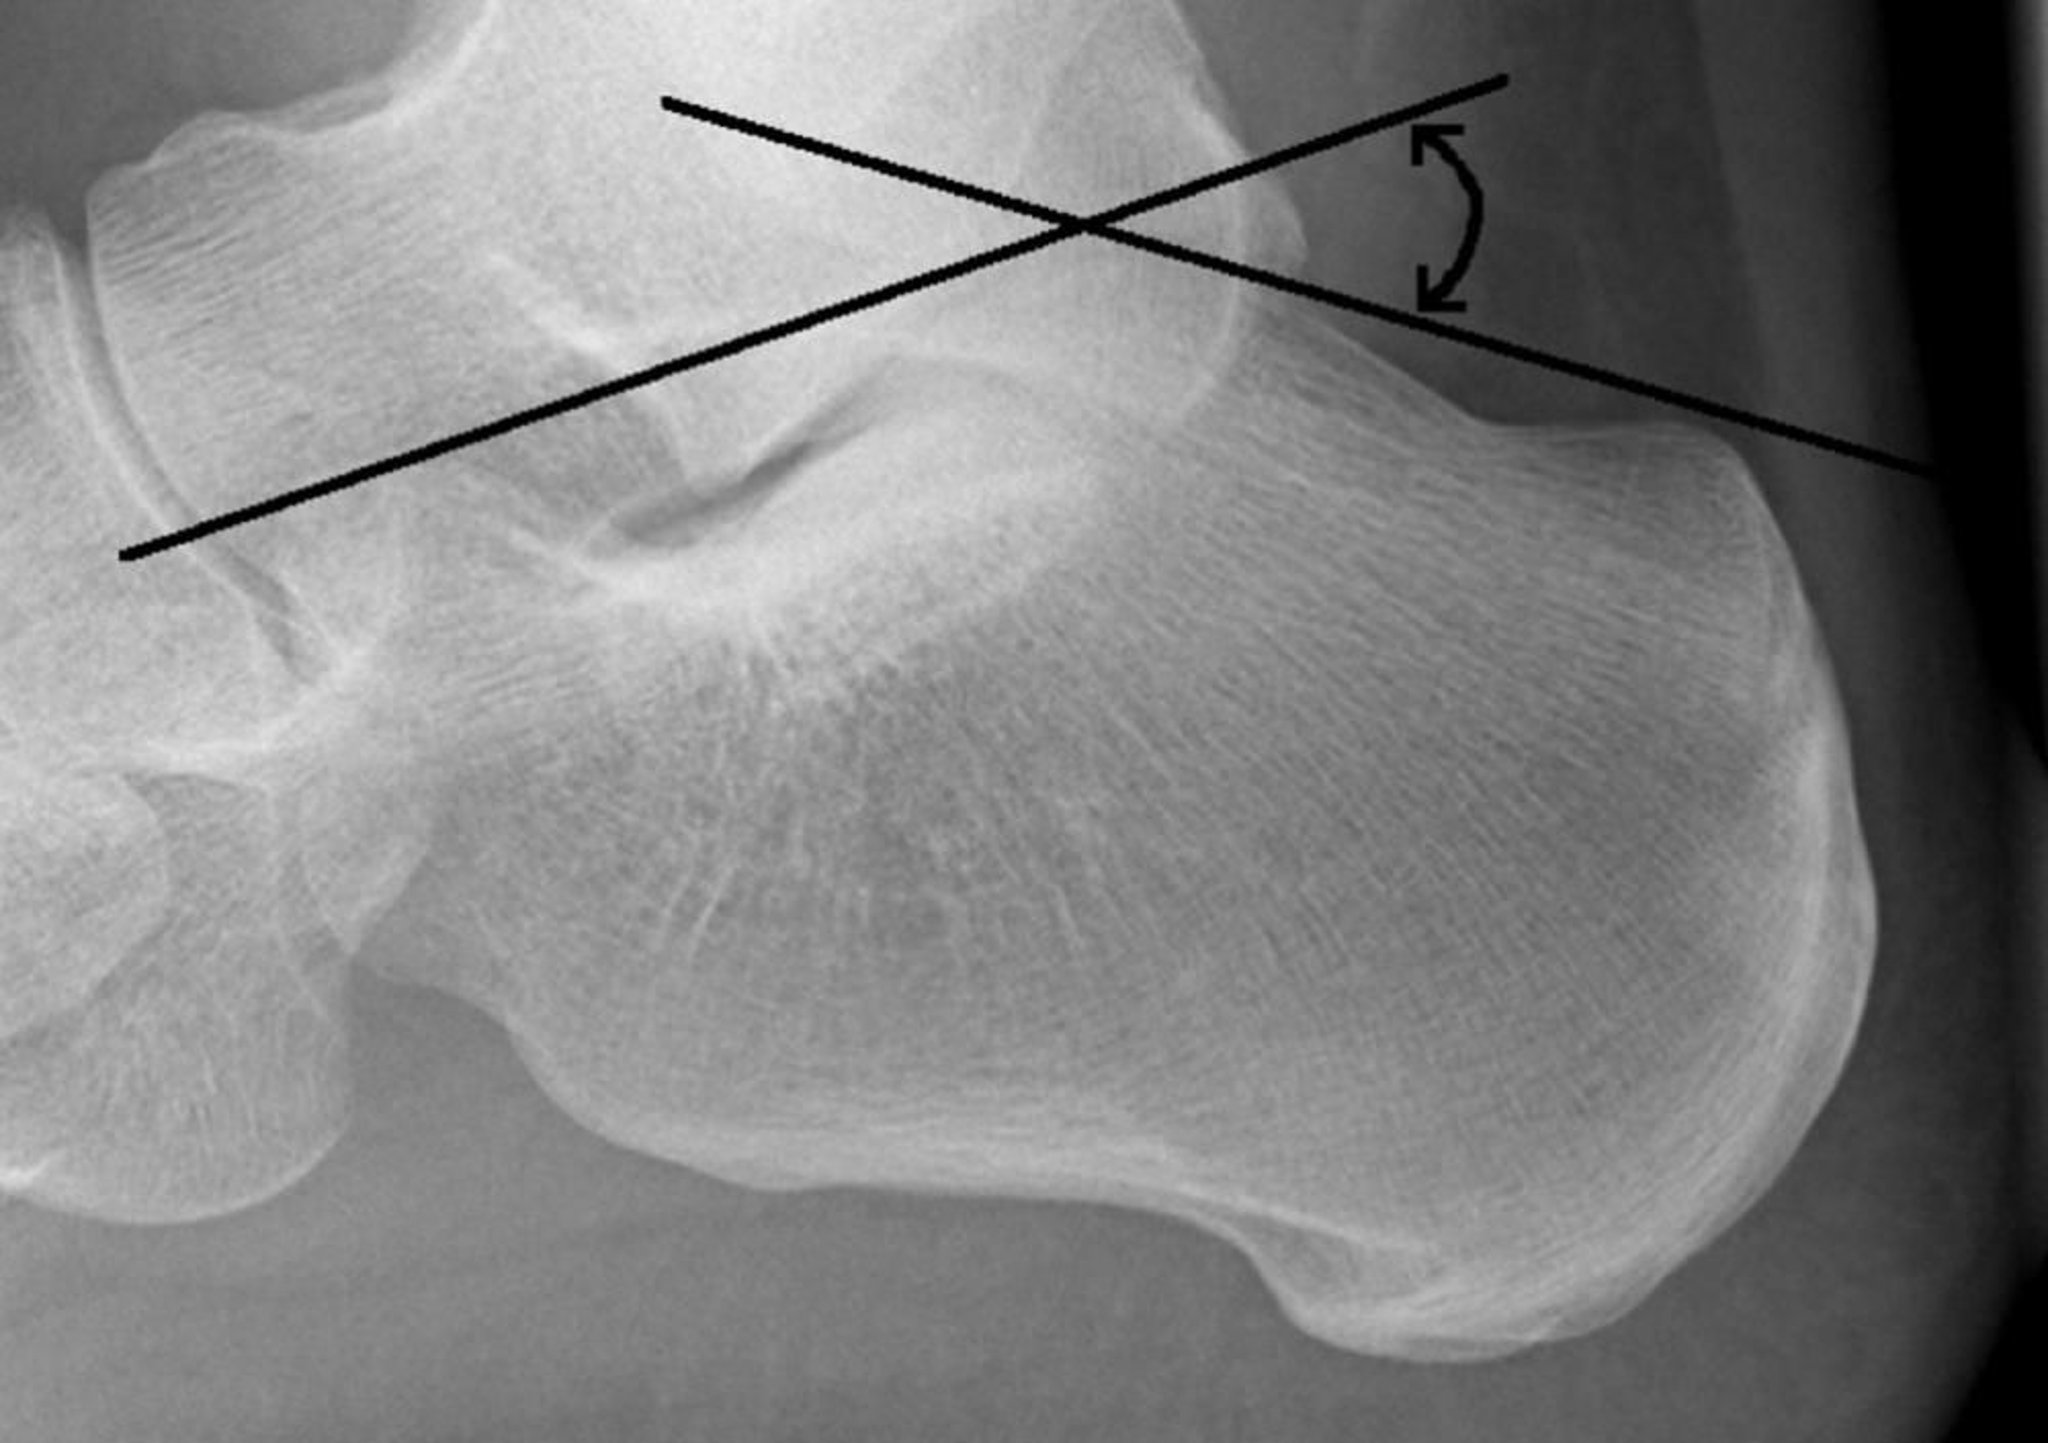

Angle de Bohler

L'angle de Bohler est formé par l'intersection d'une ligne tracée de la face supérieure de la tubérosité calcanéenne postérieure à la surface articulaire sous-talaire supérieure et une ligne tracée de la surface articulaire sous-talaire supérieure à la face supérieure du processus calcanéen antérieur. Normalement, l'angle est de 20 à 40°. Un angle < 20° suggère une fracture.

Image courtoisie de Danielle Campagne, MD.